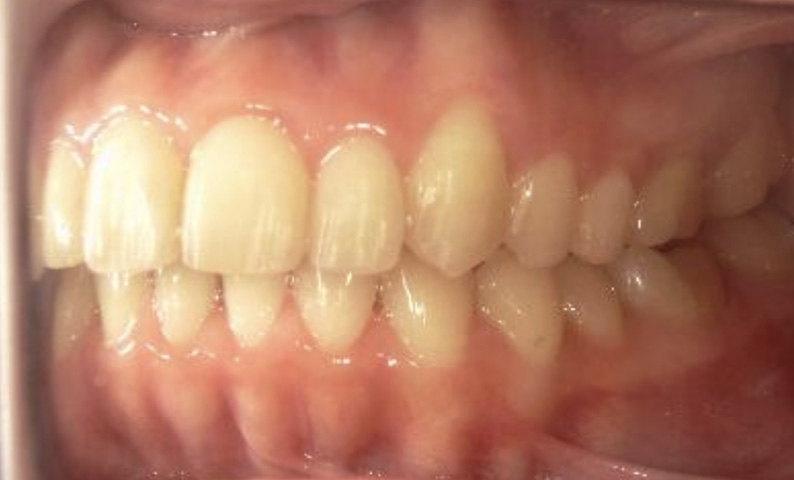

症例_001 下顎だけの部分矯正

治療期間:6ヶ月金額:27万円+税女性前歯のガタガタ下の前歯だけ

| Before | After |

|---|---|

|